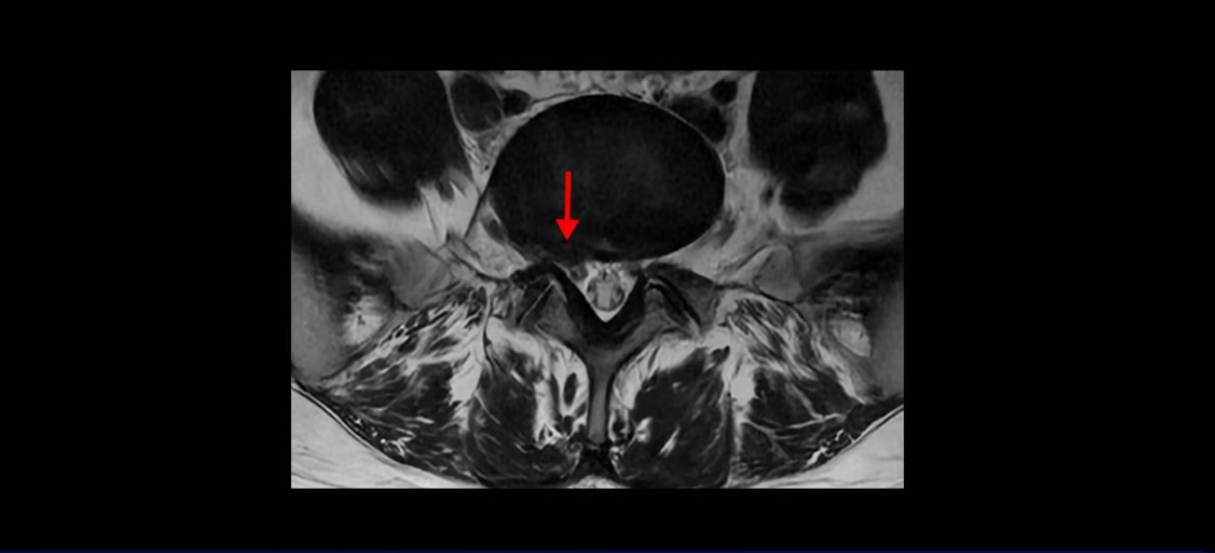

우선 이분 허리 MRI를 보면 5번 1번에 퇴행성 디스크가 있지만 방사통을 일으킬 만큼 신경을 누르고 있어 보이지 않습니다.

오른쪽으로 디스크가 약간 찢어져 보이는데, 작년에 찍은 MRI에서도 보이는 것이라 오래 전에 찢어진 후 아문 흔적으로 보입니다.

중요한 것은 오른쪽 다리에 심한 방사통이 있다든가 재채기를 못 한다거나 허리를 구부리거나 몸을 살짝 비틀 때 날카로운 통증이 없습니다. 즉, 섬유륜이 최근에 찢어진 게 아닌 겁니다.

4번 5번과 3번 4번 마디도 디스크가 중앙으로 살짝 밀려나와있지만 최근에 섬유륜이 찢어진 것도 아니고, 신경 다발을 누를 정도로 심하게 밀려나와 있는 것도 전혀 아닙니다.

양쪽 신경 가지가 빠져나가는 추간공도 충분히 넓어서 신경학적 방사통을 일으킬 여지가 없습니다.